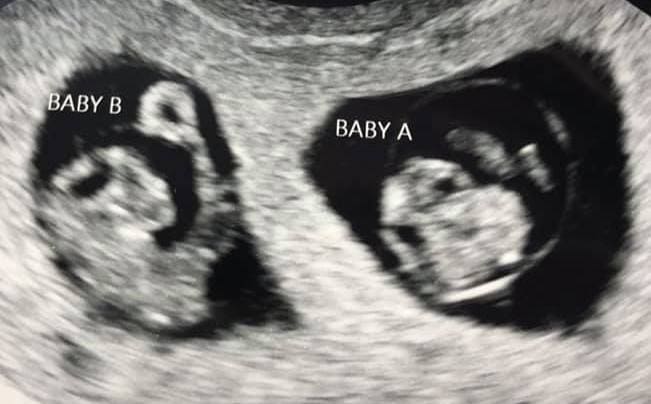

Early Twin Ultrasound at 7 Weeks

The earliest your doctor would likely order an ultrasound confirming twins would be 4 weeks pregnant. But unless you are going through fertility treatments, doing an ultrasound before 6 weeks isn’t very common, with the exception of complications. Women who are going through fertility treatments or have early complications may be able to have an early twin ultrasound at 4 or 5 weeks pregnant and find out they are pregnant with twins.

At four to five weeks after a pregnant woman’s last period the ultrasound commonly shows a small collection of fluid within the lining of the uterus that represents the early development of the gestational sac. At about five and a half weeks after a pregnant woman’s last period the ultrasound typically shows a gestational sac and within it we can see a 3-5 mm bubble-like structure, which is the yolk sac. At approximately six weeks after a pregnant woman’s last period, we can see a small fetal pole, one of the first stages of growth for an embryo, which develops alongside the yolk sac.

Can You Tell at 7 Weeks if Its Twins?

Yes! You’d need to have an ultrasound at 7 weeks to confirm a twin pregnancy. Your twin belly at 7 weeks may not look like much of a belly at all, so getting in to your doctor for an ultrasound is key to find out if you’re really having twins.